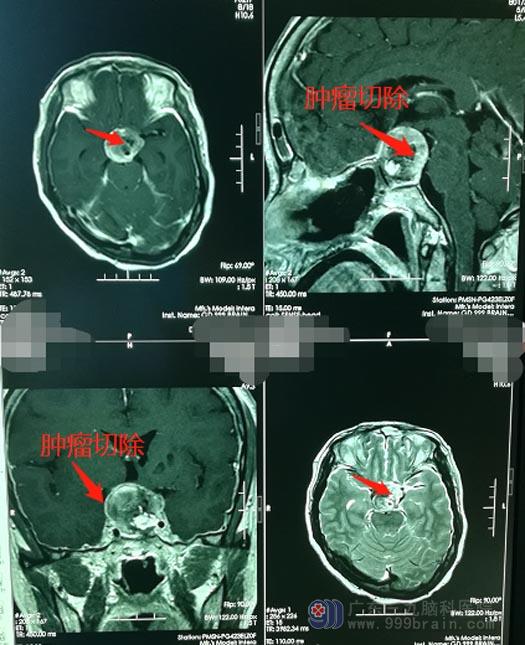

朱阿姨的家人思量着,这次一定要找一家专业的医院进行再次的治疗。入住广东三九脑科医院后,医院副院长、神经外五科主任鲁明带领手术团队决定利用神经内镜对肿瘤实行微创切除;神经内镜技术可以在很大程度上弥补当前神经外科的不足,以其广角、高清等特点,曾经无法看清或看到的解剖结构,可以像精美的画面一样呈现在医生的面前;神经内镜下经鼻微创手术切除垂体瘤,切除彻底、创伤小、恢复快,还可以保留患者的美观。

术前准备妥当后,由鲁明主刀在全麻下行“内镜经鼻蝶鞍区复发垂体大腺瘤切除术+颅底重建术”;手术顺利,术中,朱阿姨生命体征平稳,术后神志清醒、病情稳定。复查提示肿瘤已全切。